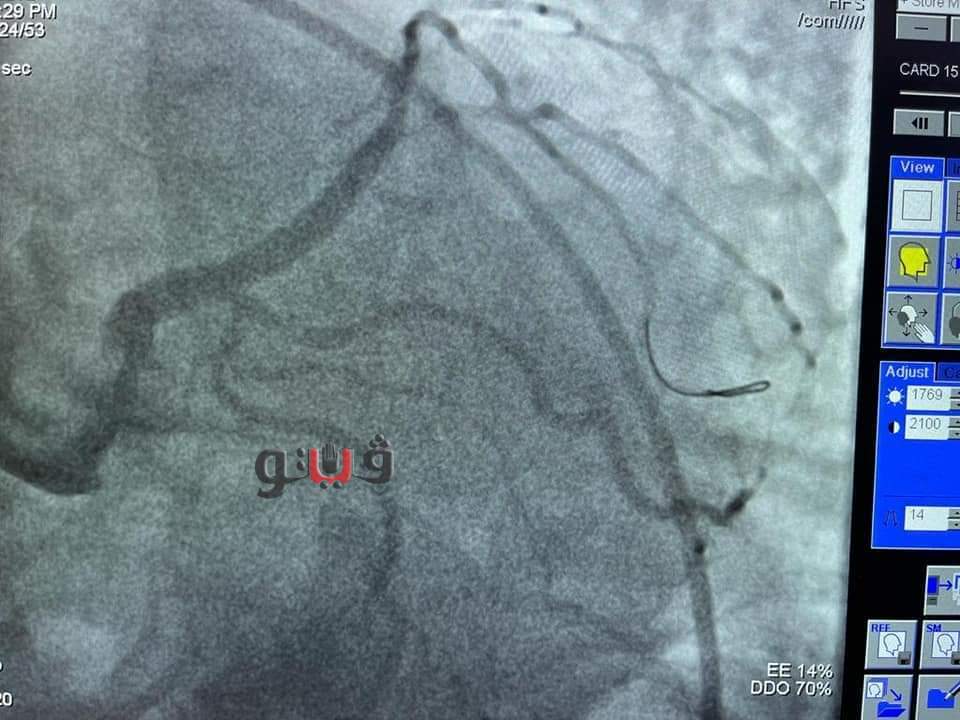

شهد مجمع الإسماعيلية الطبي، التابع لهيئة الرعاية الصحية، اليوم الثلاثاء، إجراء جراحة ناجحة عن طريق إجراء قسطرة قلبية لمسنة تبلغ من العمر ٧٢ عاما باستخدام المنظار الداخلي (I VUS) ، وذلك "دون تحمل المريضة لأي تكاليف" بقيادة الدكتور طارق رشيد، أستاذ القلب والقسطرة القلبية وخبير مرضى الانسداد المزمن للشرايين التاجية.

وكانت المريضة تعاني من ضيق شديد الخطورة بنسبة 95% بالجذع الرئيسي الأيسر للقلب وتم إنقاذها بعد معاناة لمدة أسبوع كامل بحثًا عن مكان تجري فيه جراحة قلب مفتوح أو تركيب دعامات ومبلغ يفوق ال 100 ألف جنيه للعلاج بأحد المستشفيات الخاصة، وكادت أن تفارق الحياة نظرًا لخطورة حالتها الصحية الشديدة.